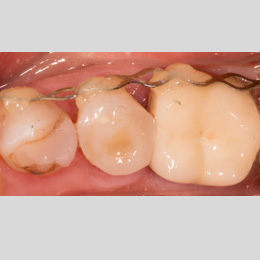

Fallbeispiel: Zahn 15 mit starker Krümmung

Jeder Zahn ist einzigartig – in diesem Fall zeigte sich Zahn 15 mit einer starke Wurzelkrümmung. Trotz der starken Krümmung konnte eine Wurzelkanalbehandlung durchgeführt werden und somit auch die Brücke erhalten werden.